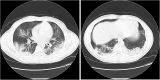

Coronavirus 2 (SARS-CoV-2) is now considered a pandemic causing Coronavirus disease (COVID-19), multiple fatalities and morbidities which have been associated with it worldwide. We report a severe pneumonia causing acute respiratory distress syndrome due to a coinfection with SARS-COV-2 and Parainfluenza 4 virus in a Hispanic 21 year old male in Florida, USA. The case represents the importance of prompt diagnosis and awareness of the potential co-infection with other respiratory viruses and this novel deadly virus.